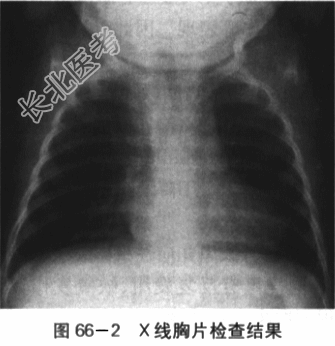

患儿,男,2岁3个月,因"哭吵后口唇发绀伴气促1h"就诊。患儿入院前1h剧烈哭吵后出现口唇发绀、呼吸急促、家属安抚后无明显改善,送入急诊。出生6月龄前患儿无特殊病史,6月龄后患儿偶有哭吵后口唇青紫,增有剧烈哭吵后呼吸快,口唇发紫加重,安抚后好转;在当地住院发现有心脏杂音,做了一些检查后诊断心脏病(具体不详)。平素活动量少,喜静不喜动,喜抱,偶尔有走路时反复下蹲。目前饭虽少,身高、体重均不及同龄儿。大小便正常。患儿为G₁P₁,孕39周自然分娩。BW3200g。否认孕期感染或服药史,否认围产期窒息缺氧病史。否认家族心脏病或其他遗传病史。体格检查:T37℃,P148次/min,R52次/min,BP78mnlHg/40mmHg,Wt10.1kg,Ht78cm,SaO₂68%。烦躁,全身大汗,口唇发绀,可见杵状指,四肢脉搏稍弱,对称。肺部检查两肺呼吸音粗稍粗,未及明显啰音。心前区饱满,心尖搏动位于第4肋间左乳线上,范围约2cm;HR118次/min,规则,2~3LSB SMⅠ~Ⅱ级,粗糙,P2略增强,无分裂。腹部平软,肝脏肋下2.5cm,质地软。脾未触及。双下肢无水肿。实验室检查(1)心电图检查:窦性节律,右房、右室增大。电轴右偏,Ⅱ导联P波高尖,呈双峰,时限=0.12s。V₁导联QRS波群呈R形,V₅导联QRS波群呈RS形;ST段压低,V₃~V₅导联T波倒置。如图66-1所示。(2)X线胸片检查:右房、右室大。心胸比例0.65,心影呈"靴型"心,心尖圆钝、上翘;肺动脉端内凹,肺血少。如图66-2所示。(3)超声心动图检查:心脏位置及连接正常。右房、右室增大,右室壁肥厚,左室收缩活动正常。主动脉增宽,骑跨于室间隔上50%。左右冠状动脉开口可见,肺动脉瓣及瓣下狭窄,瓣环0.67cm,总干内径1.29cm,流速2.3m/s,右室流出道狭窄肌肉肥厚,过此处血流少,流速约2.8m/s。左肺动脉开口0.82cm,内径0.97cm;右肺动脉开口10.78cm,内径0.85cm。房室瓣开放活动可。房间隔完整。室间隔缺损,对位不良型,双向分流。左位主动脉弓。如图66-3所示。